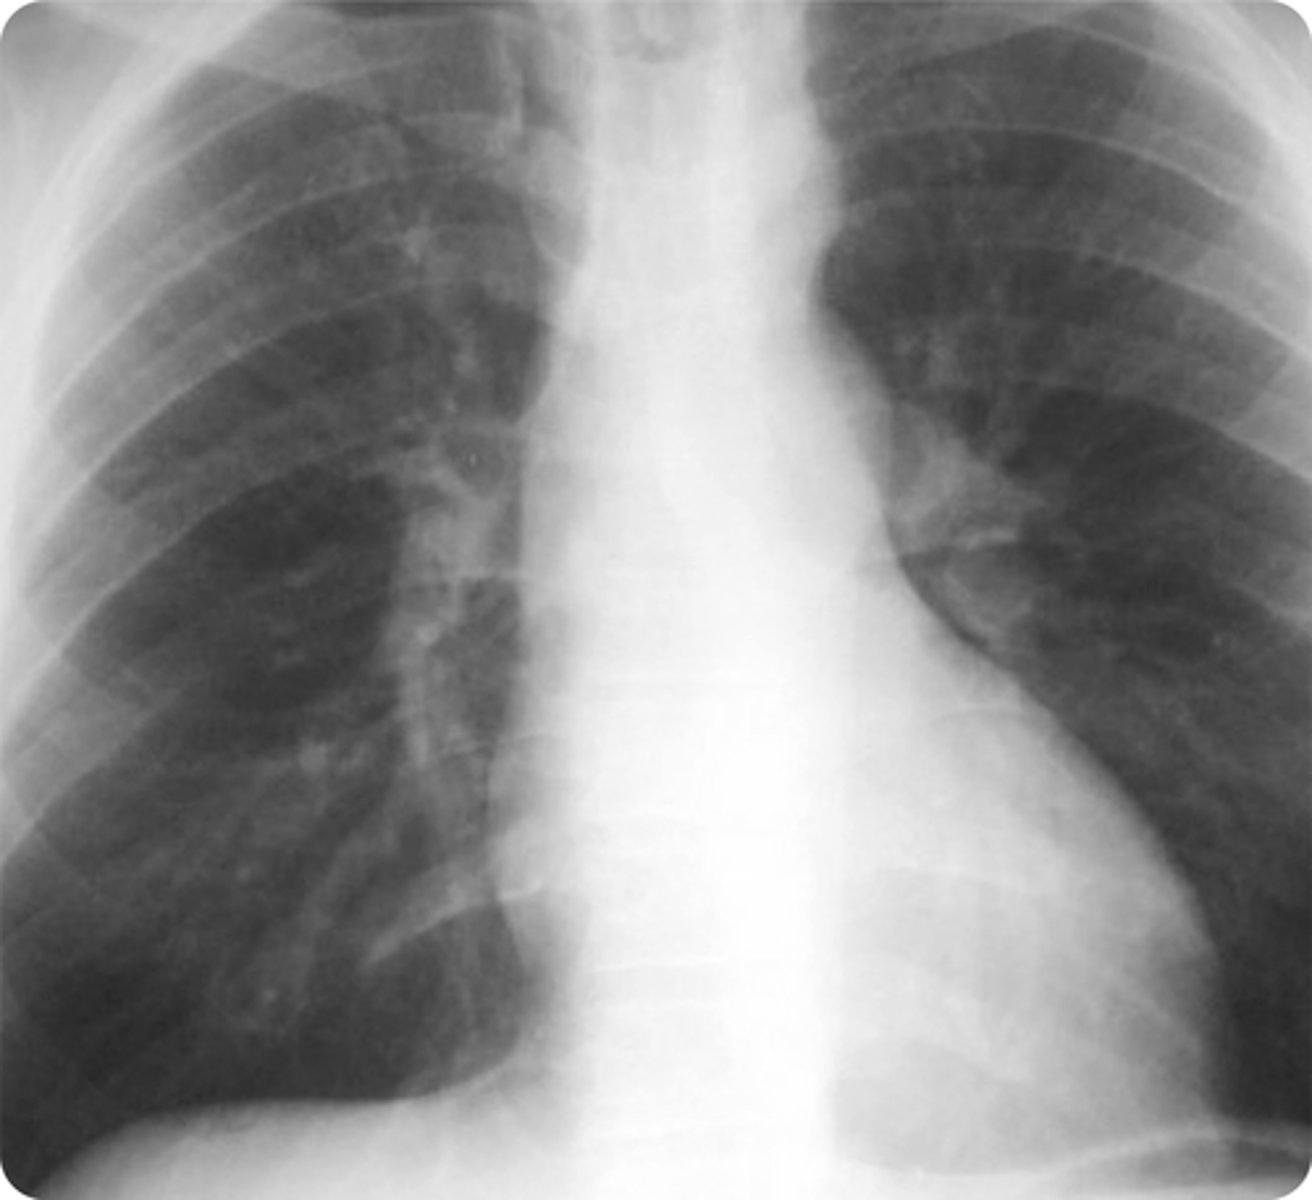

Delayed femoral pulse when compared to the brachial pulse

**coarctation of the aorta

A 14-year-old boy without significant medical history presents with his parent to clinic with concern for cold extremities, pain in his legs with exercise, and intermittent chest pain for the past month. Vital signs today include a heart rate of 66 bpm, respiratory rate of 18/min, oxygen saturation of 97%, and temperature of 98.8°F. Chest X-ray is shown above. Which physical exam finding is most likely to be present in the patient’s suspected condition?

ADelayed femoral pulse when compared to the brachial pulse